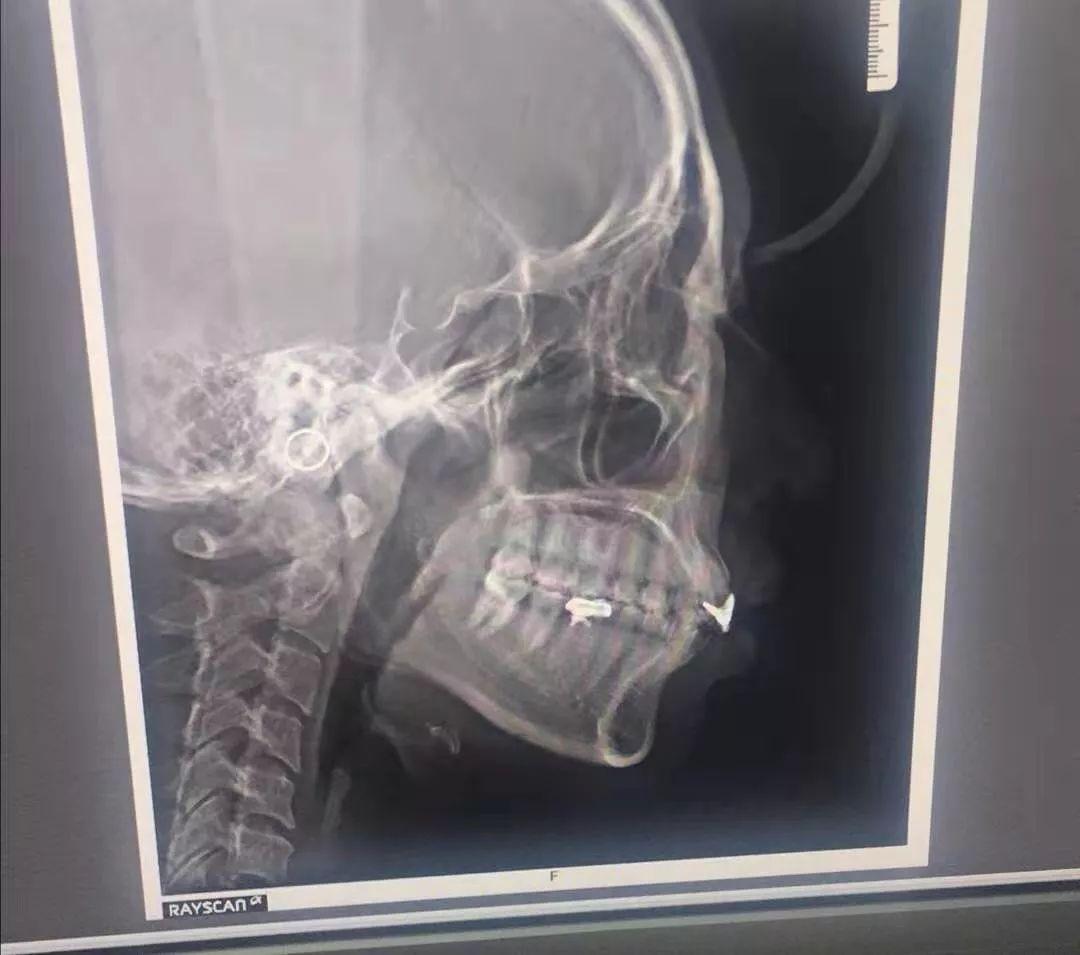

牙齒 X 光片

醫(yī)生說我原本補過牙,不適合傳統(tǒng)牙齒矯正,而且隱形矯正還能幫我矯正牙齦突出的問題。這簡直是天大的好消息!